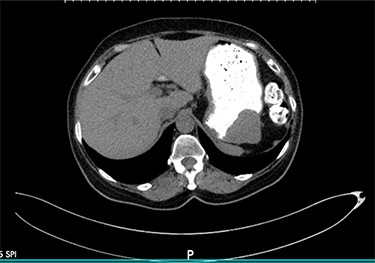

We present the case of a 68-year-old female patient with a history of hypertension and hypothyroidism who was being evaluated at the surgery clinics due to complains of a left inguinal bulging concerning for a hernia. She denied abdominal pain, nausea, vomiting or any other symptoms related to the GI tract. Abdominopelvic computed tomography (CT) scan with oral contrast was ordered for further evaluation. Imaging results were remarkable for a well-circumscribed soft tissue submucosal mass in the gastric body, measuring 4.4 × 4.3 × 3.2 cm (Fig. 1). There was no evidence of transmural invasion or lymphadenopathy, and the rest of the GI tract was within normal limits. Subsequently, the patient underwent esophagogastroduodenoscopy with endoscopic ultrasound (EUS) and fine needle aspiration (FNA). EUS was remarkable for a hypoechoic upper stomach lesion, arising from the muscularis propia of the gastric wall and measuring 4 cm. Based on EUS results, the lesion was suspicious for a GIST. The first FNA was non diagnostic, and another biopsy with tattooing of the lesion was performed. The second FNA was positive for a spindle cell neoplasm, consistent with schwannoma.

Axial view of the abdominopelvic CT scan with oral contrast showing a well-circumscribed gastric soft tissue attenuation. P: Posterior.